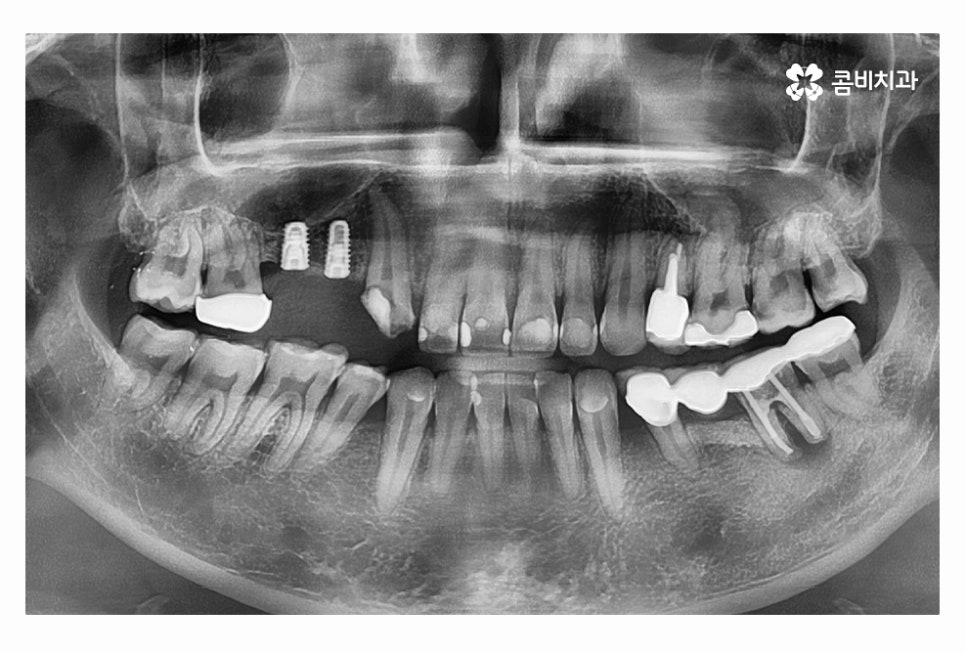

20대임플란트 치료를 하시는 분들의 경우 충치, 사고 등으로

치아를 잃게 되는 경우가 많기 때문에 치료는 크게 어려운 경우는 많지 않지만

당뇨나 전신질환 등이 있거나 잇몸 상태가 좋지 않은 경우에는

20대라고 하더라도 보다 섬세한 치료가 중요하다고 할 수 있어요.

임플란트의 치료 계획은 치아를 잃게 된 원인부터 잇몸 상태,

전신질환 여부, 회복력 등을 고려하여 1:1로 맞춤 치료 계획을 세우며